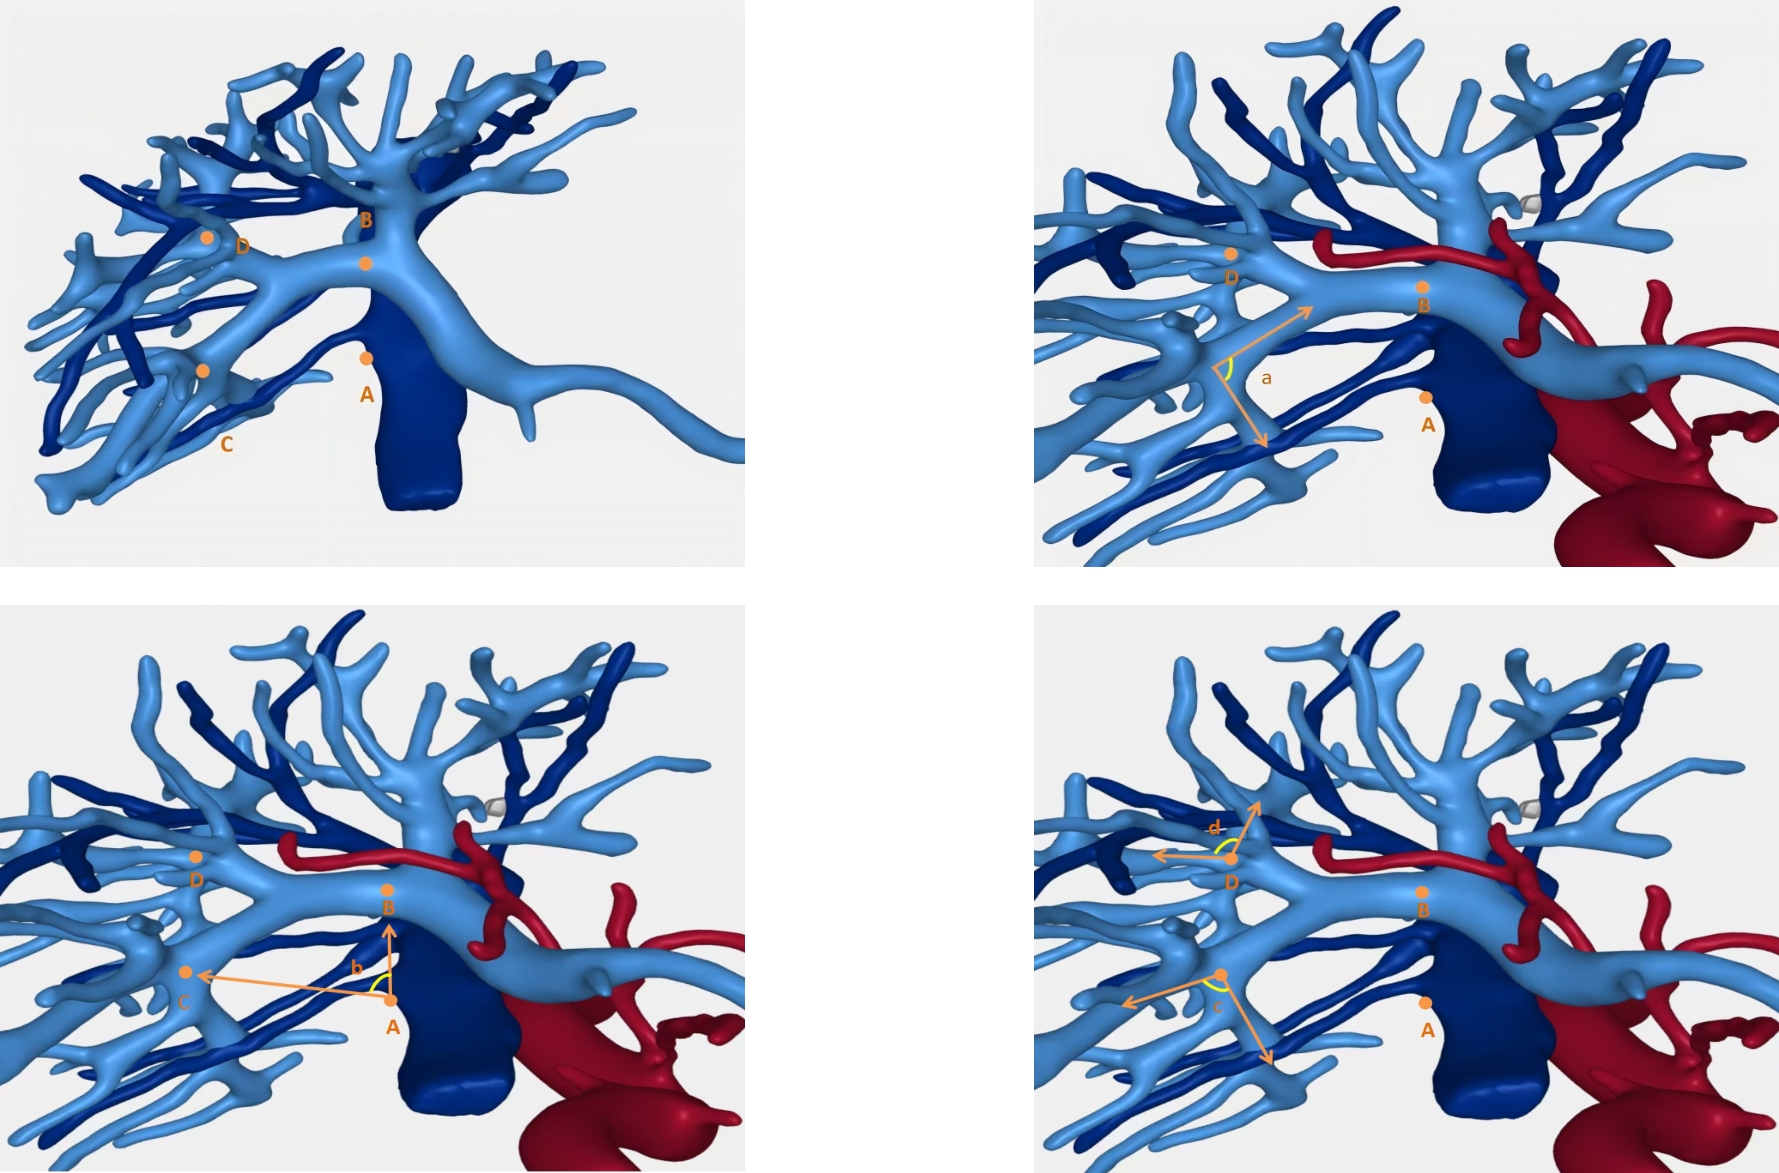

• Applied anatomy of segmental Glissonian pedicles at the hepatic hilum guided by the Laennec's membrane concept and its value in laparoscopic surgery

Abstract:Background and Aims Precise identification and control of segmental Glissonian pedicles are fundamental to laparoscopic anatomical liver segmentectomy. However, marked anatomical variations, particularly in the right hemiliver, pose significant technical challenges. Based on the anatomical concept of the hepatic Laennec's membrane, this study aimed to systematically investigate the applied anatomy of Glissonian pedicles at the hepatic hilum and to establish practical anatomical landmarks for laparoscopic anatomical liver resection.Methods Six intact adult human liver specimens without macroscopic lesions were dissected under the guidance of the Laennec's membrane concept. The segmental Glissonian pedicles at the first porta hepatis were meticulously isolated, and the intervening liver parenchyma was removed. The origin, branching patterns, and spatial courses of Glissonian pedicles in each hepatic segment were analyzed. For the right hemiliver, a localization system consisting of four anatomical landmarks, two reference lines, and four characteristic angles was proposed and quantitatively evaluated using specimen measurements combined with CT imaging and three-dimensional liver reconstruction.Results The intrahepatic Glissonian system demonstrated both consistent patterns and pronounced individual variations. In the left hemiliver, the Glissonian pedicles of segments Ⅱ and Ⅲ usually arose independently, while segment Ⅳ commonly presented a bifurcated pattern with occasional multiple branches. In contrast, the right hemiliver showed substantial variability: segment V pedicles were frequently multibranched and often received contributions from segment Ⅵ; segment Ⅵ served as a pivotal pedicle with multiple branches contributing to segments V and Ⅶ; segment Ⅶ most commonly originated from the root of the right posterior pedicle, although in some cases it was formed by distal extensions of segment Ⅵ; segment Ⅷ pedicles were relatively constant in morphology, typically consisting of one or two branches. The proposed anatomical landmarks and quantitative parameters enabled clearer spatial localization of segmental Glissonian pedicles in the right liver.Conclusion Systematic dissection of segmental Glissonian pedicles guided by the Laennec's membrane concept, together with a quantitative anatomical landmark system, enhances the understanding of their spatial anatomy and variations. This approach provides practical and reliable anatomical guidance for precise and safe laparoscopic anatomical liver segmentectomy.